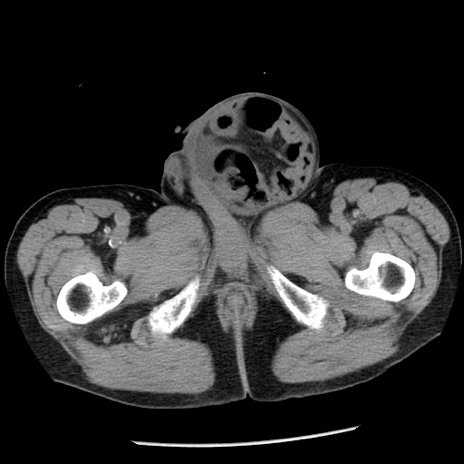

症例26(横断像)

【症例】80歳代男性

【主訴】嘔吐

【現病歴】昨晩2回嘔吐あり、今朝になっても嘔吐あり。来院。

【既往歴】胃潰瘍

【身体所見】意識清明、BT 37.6℃、BP 166/95mmHg、HR 100bpm、SpO2 97%、腹部:平坦・軟、腸蠕動音聴取良好、圧痛なし。

【データ】WBC 21900、CRP 1.46